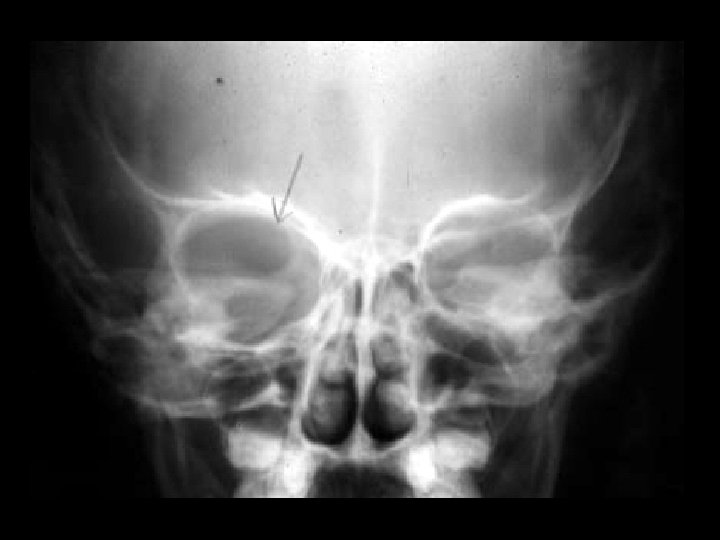

Neurofibromatosis type I • Findings: – partially empty orbit = sphenoid wing dysplasia • ddx: – lytic metastasis – osteomyelitis